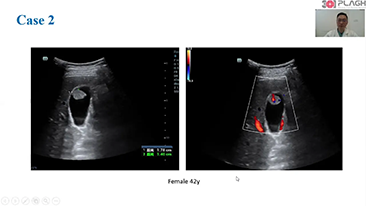

Hoogwaardig ultrasoundsysteem voor radiologie

Aangestuurd door de revolutionaire ZONE Sonography-technologie, tilt de Resona R9 klinische intelligentie naar een hoger niveau met een complete oplossing.